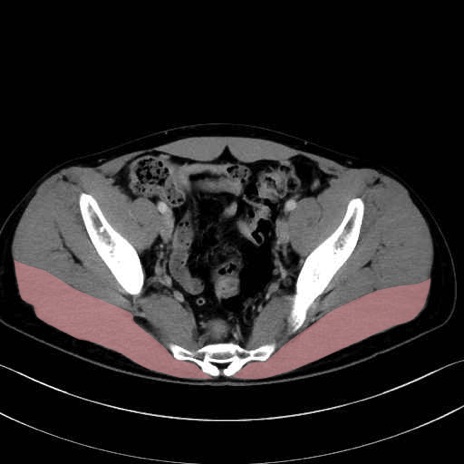

大殿筋 (Gluteus maximus)